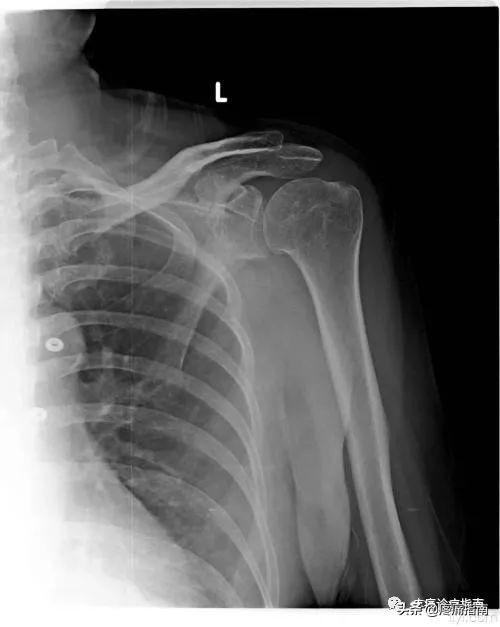

影像检查:急性期X线检查一般呈阴性,慢性期X线平片可见到肩部骨质疏松,或冈上肌腱、肩峰下滑囊钙化征。

肩周炎急性期:起病急骤,疼痛剧烈,肌肉痉挛,关节活动受限。夜间痛剧,压痛范围广泛,喙突、喙肱韧带、肩峰下、冈上肌、肱二头肌长头腱、四边孔等部位均可出现压痛。急性期可持续2~3周。X线检查一般呈阴性。

肩关节结核:常伴发肺结核。有低热、消瘦等全身症状。多发于成年人,亦可发生于任何年龄。血沉快,可达50mm/h以上。X线片可见骨质明显疏松、骨质破坏及坏死形成,甚至出现肩关节半脱位。